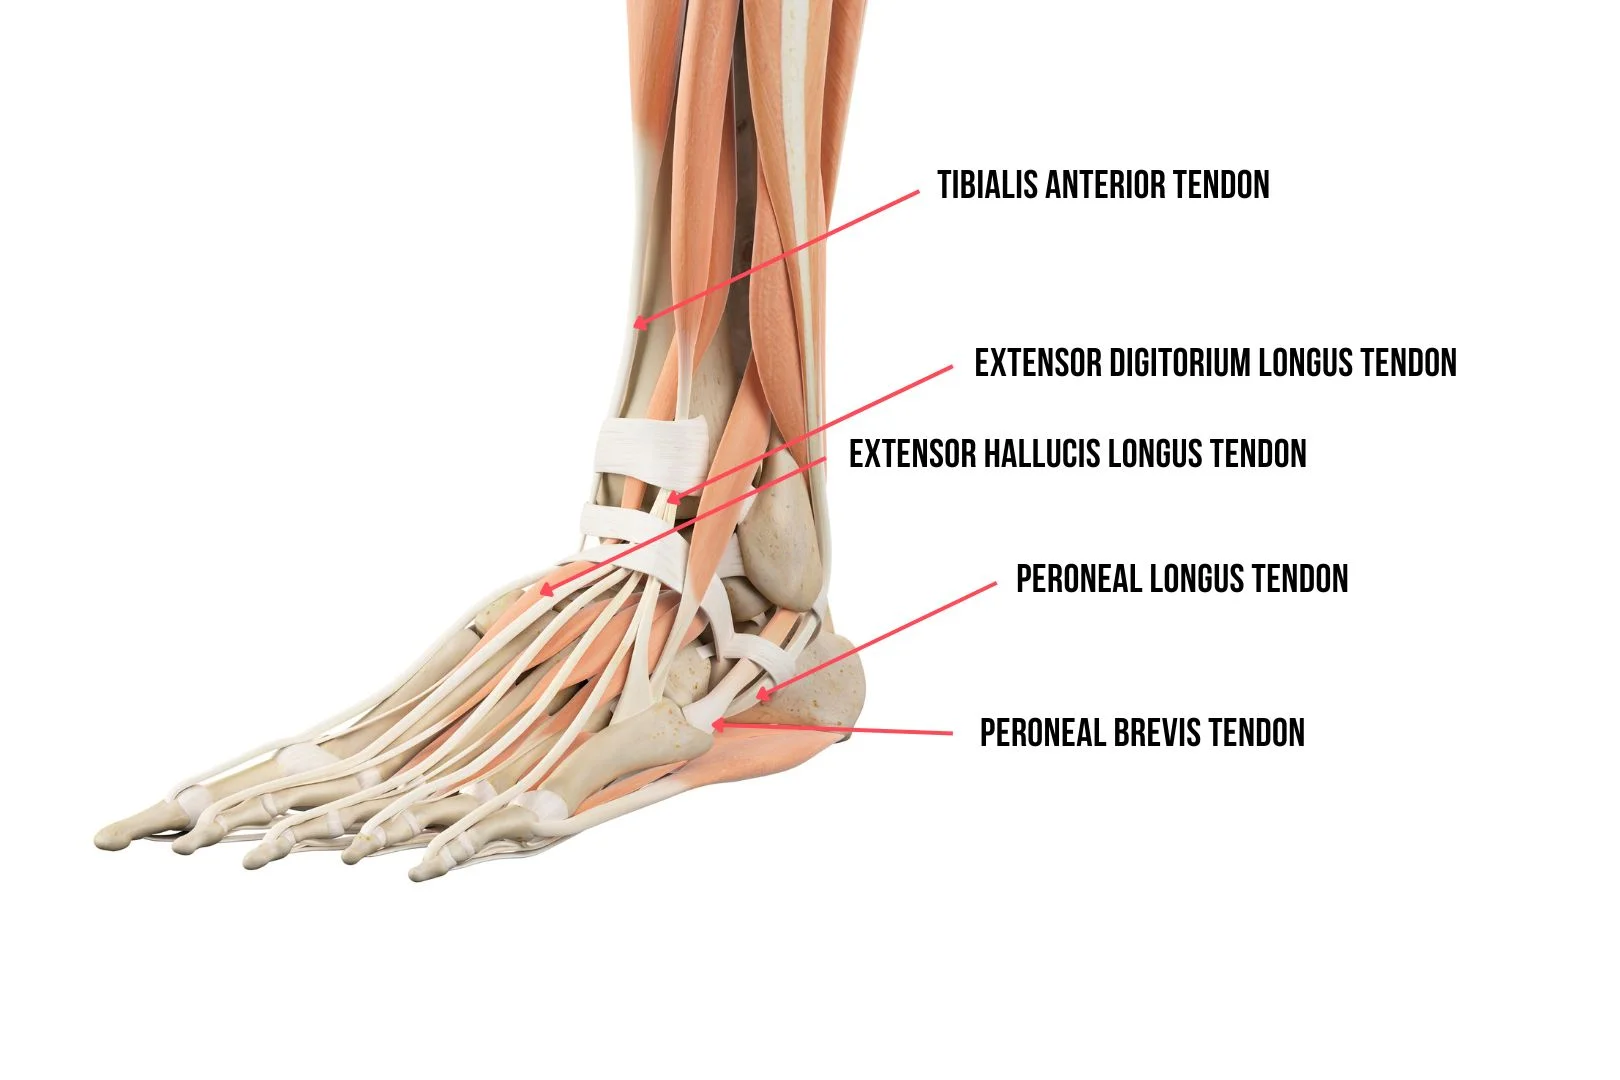

肌腱

肌腱就像连接肌肉和骨骼的强力橡皮筋。跟腱是整个踝关节解剖结构中最大的肌腱,它连接小腿肌肉和跟骨。当您行走或跑步时,它可以帮助您蹬地。踝关节周围的其他重要肌腱包括:

1. 胫骨前肌腱

2. 胫骨后肌腱

3. 趾长伸肌腱

4. 趾长伸肌腱

5. 腓骨长肌腱

6. 腓骨短肌腱

7. 拇长屈肌腱

8. 趾长屈肌腱